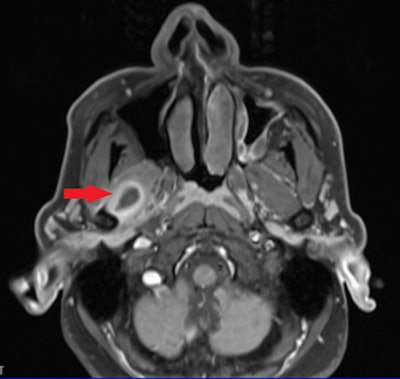

Further evaluation for persistent pain revealed a provisional diagnosis of TMD, which worsened despite conservative treatments. Consultations with an ear, nose, and throat specialist and a neurologist, including magnetic resonance imaging (MRI), identified a cystic lesion in the right lateral pterygoid muscle that was suspected to be cysticercosis, the authors wrote.

The axial section of the MRI shows a ring-enhancing lesion within the left lateral pterygoid muscle, suggestive of cysticercosis. Image courtesy of KV and colleagues. Licensed under CC BY 4.0.

Furthermore, initial treatment with albendazole was unsuccessful, prompting surgical exploration. An excisional biopsy confirmed the diagnosis of cysticercosis, and postoperative albendazole therapy led to symptom resolution. Follow-up at three months showed no recurrence or complications, with the prognosis being excellent, they wrote.